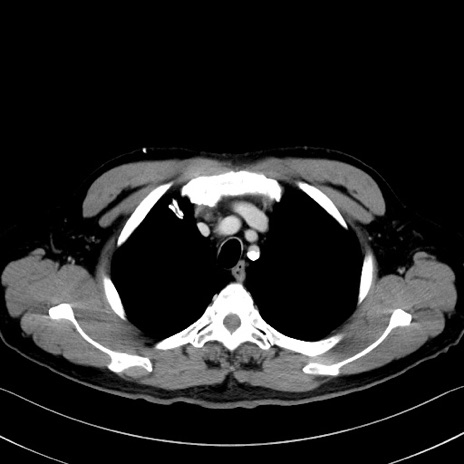

症例35(横断像)

【症例】70歳代 男性

【主訴】腹部膨満、嘔吐

【現病歴】昨日より腹部膨満感出現。本日増悪し、仙痛出現。嘔吐あり、受診。

【既往歴】糖尿病、胆摘後

【身体所見】BP 149/80mmHg、HR 74/min、BT 35.9℃、腹部:膨満、軟、圧痛なし。腸雑音減弱あり。上腹部正中切開瘢痕あり。

【データ】WBC 13500、CRP 1.72